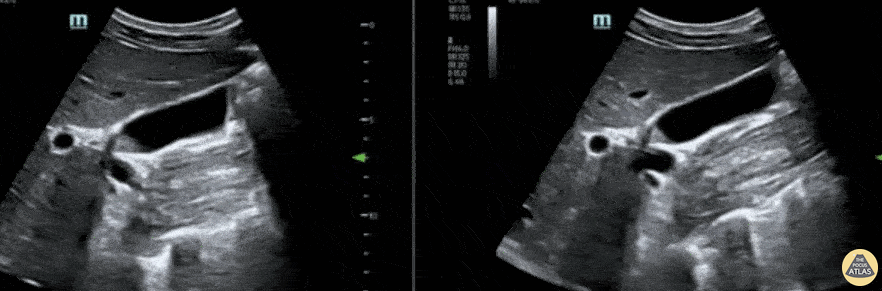

Biliary - Gallbladder Polyp

51 year old male with a chief complaint of RUQ abdominal pain for 3 days with associated nausea and vomiting. The curvilinear probe was used to evaluate the gallbladder for stones or other pathology. A gallbladder polyp at the neck was discovered (also subsequently confirmed on abdominal CT). Lindsay Davis, DO, MPH, @Lindsadavis18 Lydia Mansour, DO Emily Nagourney, MS4 Central Michigan University